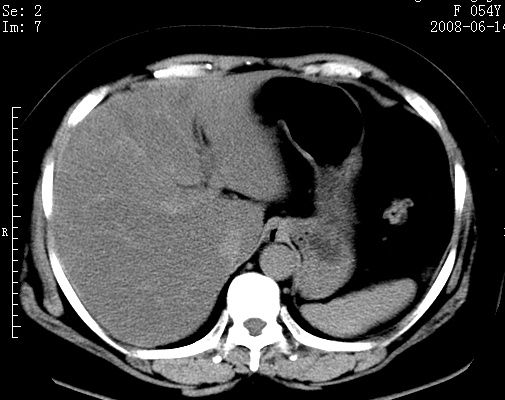

标题: CT14033:F54Y,来源哪? 外伤发现,自述既往无不适。 [打印本页]

标题: CT14033:F54Y,来源哪? 外伤发现,自述既往无不适。

1、脂肪肝。2、腹腔囊性占位,首考虑来源于右肾下极,其次考虑来源于肠系膜。

1、脂肪肝。2、腹腔囊性占位,首考虑肠源性囊肿或中肾管囊肿。

脂肪肝,巨大肾囊肿

1)脂肪肝。2)右肾下极巨大囊肿。

右中下腹部囊性肿块,与右肾下极关系密切,考虑右肾下极巨大外生性囊肿;脂肪肝。